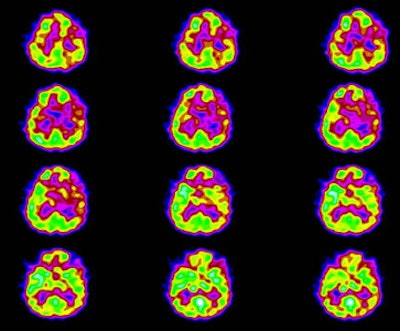

Patients with Lyme encephalopathy generally show a poor response to medications that would ordinarily be helpful and the patient's psychiatric findings can improve with antibiotic treatment alone [8]. Lyme encephalopathy most commonly produces a multifocal pattern of hypoperfusion affecting both the cortex and deep structures [6,8]. Significant perfusion abnormalities can be identified in up to 50% of affected patients [8]. Diffusely reduced cerebral cortical flow has also been described [7]. SPECT imaging can also be used to monitor response to therapy as areas of abnormal perfusion can reverse with treatment [6].

Neuro lyme: The patient below complained of intermittent right facial numbness, memory loss, and change in personality. Lyme titers were positive. MR imaging of the brain demonstrated no anatomic abnormality. SPECT imaging revealed multifocal areas of decreased perfusion in a pattern consistent with Lyme encephalopathy. |

|